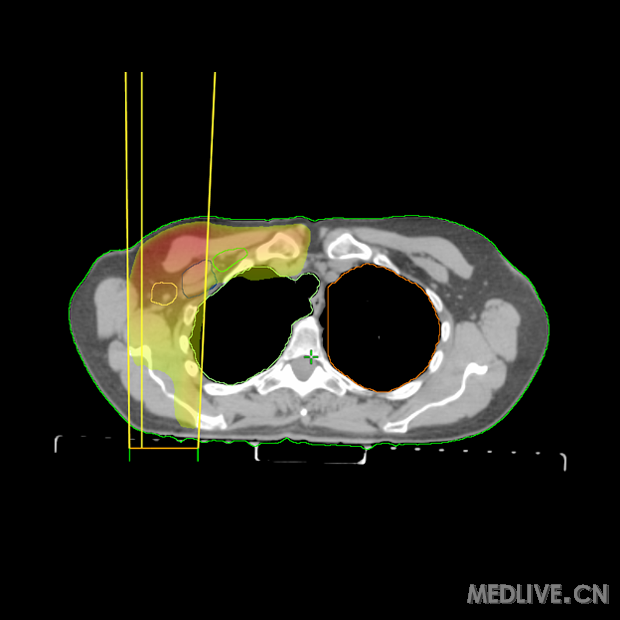

晚期乳腺癌CT图片_圈子_医脉通

晚期乳腺癌CT图片_圈子_医脉通